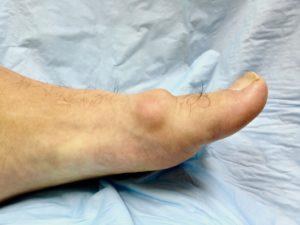

As the condition progresses, the body lays down additional bone around the joint margins, which restricts the movement and can obliterate it all together. As the arthritis in the joint gets worse, as shown in the picture below, the treatment options change. In severe cases, conservative care can be less helpful and it is often difficult to save the joint.

This procedure is used when the joint is not painful but the bony outgrowth results in footwear irritation. The bony growth is removed producing a smooth profile to the joint. There is a risk that the joint may become painful as the range of motion in the joint might increase.